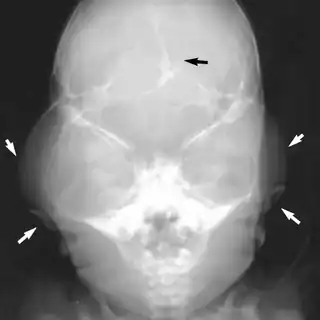

Severe temporal bulging arrows), lacunar skull black arrow, low-set ears with angulated posteriorly arrows